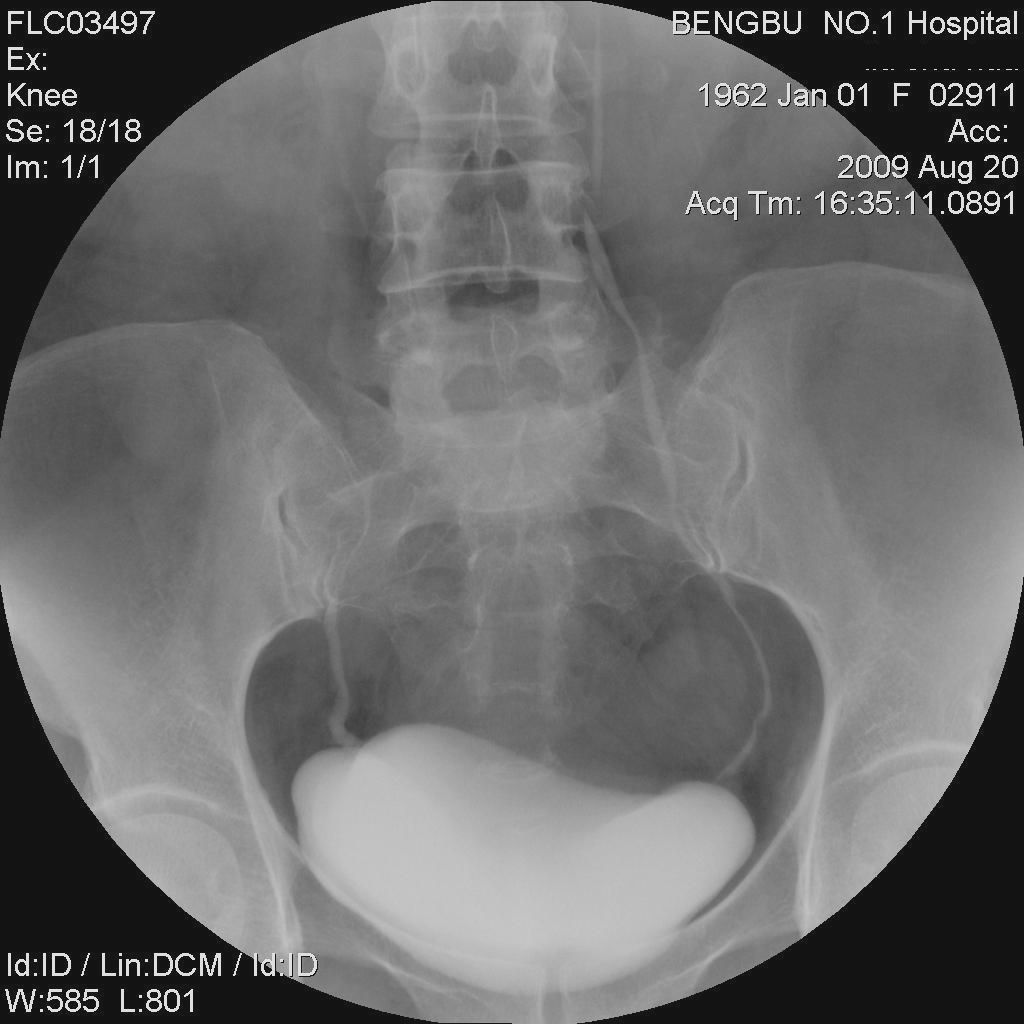

以下是引用黑白光影在2009-9-11 11:32:00的发言:[br]右肾积水,原因不明,不排除外压所致。输尿管与第4腰椎水平段除第6张略有显影外,其余均为空白,为重点怀疑部位。(迷走血管或腔脉后输尿管?)

以下是引用拾荒者在2009-9-11 20:33:00的发言:[br]右侧肾盂、肾盏积水扩张,肾盂输尿管移行区缩窄过于突然,建议结合b超或ct检查。

以下是引用子期在2009-9-11 21:51:00的发言:[br]考虑右肾及右输尿管结核可能性大。